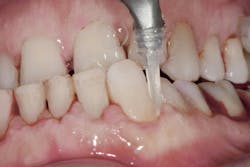

Air polishing accesses challenging areas more efficiently1,7 (figure 1) and reduces biofilm levels in periodontal pockets significantly more than hand-activated instrumentation.1,4,6 The PWR Pair offers the advantage of two powders:

- Sodium bicarbonate powder for the removal of heavier stain supragingivally Glycine powder for supra/subgingival access with a standard nozzle that reaches PD up to 4 mm and subgingival nozzle for PD up to 5 mm.1 A flexible narrow tip is attached to the subgingival nozzle to allow for subgingival access with minimal tissue distention (figure 2).1,3,6